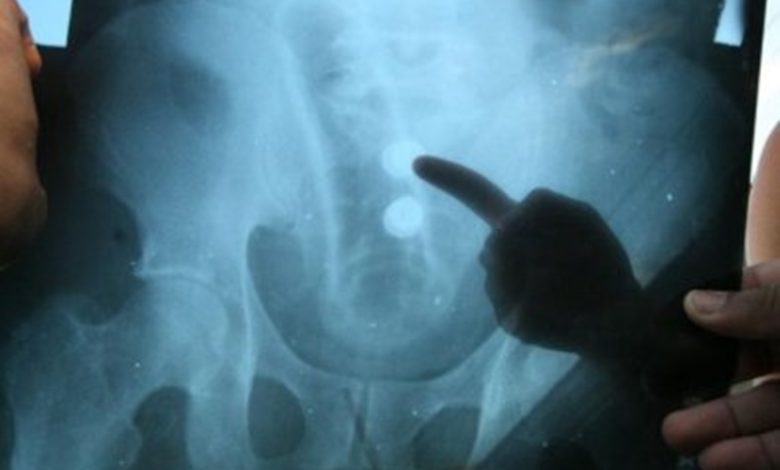

Um momento de prazer terminou em dor e constrangimento na terça-feira (14), em Sorriso (420 km de Cuiabá). Ocorre que um homem de 32 anos precisou de atendimento médico depois que um brinquedinho sexual acabou entalando no ânus dele.

Segundo o site JK Notícia, que cobre a região, o próprio homem que introduziu o objeto, mas o vibrador acabou se deslocando para dentro do reto e não pôde mais ser retirado. Sem conseguir resolver a situação sozinho, ele foi levado ao Hospital Regional.

Após atendimento médico, o objeto foi retirado e o paciente recebeu alta.